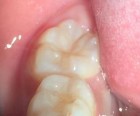

Bệnh nhân: Ng. Bá Tuấn Đ. 6 tuổi, răng 36, mã BA 6320/17

Sau sáu tháng. ICDAS: 2; Di: 21 | Sau chín tháng. ICDAS:1; Di: 19 | Sau 12 tháng. ICDAS: 1; Di: 14 |